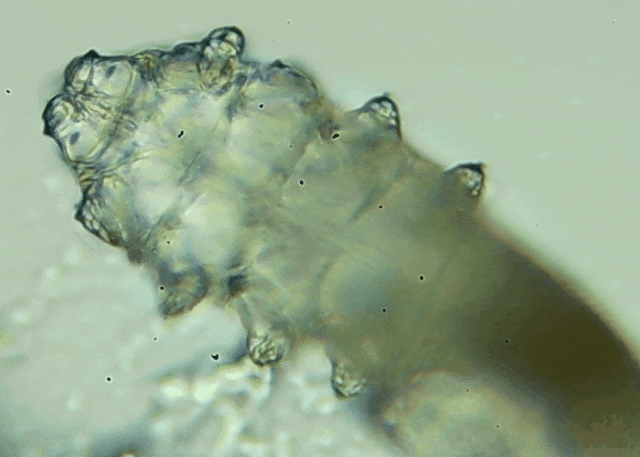

我只是眼睛癢,結(jié)果醫(yī)生說(shuō)我睫毛里有80只蟲(chóng)?這不是恐怖片,而是真實(shí)的病例:武漢一13歲男孩,右眼9根睫毛里檢出39只螨...[詳細(xì)]